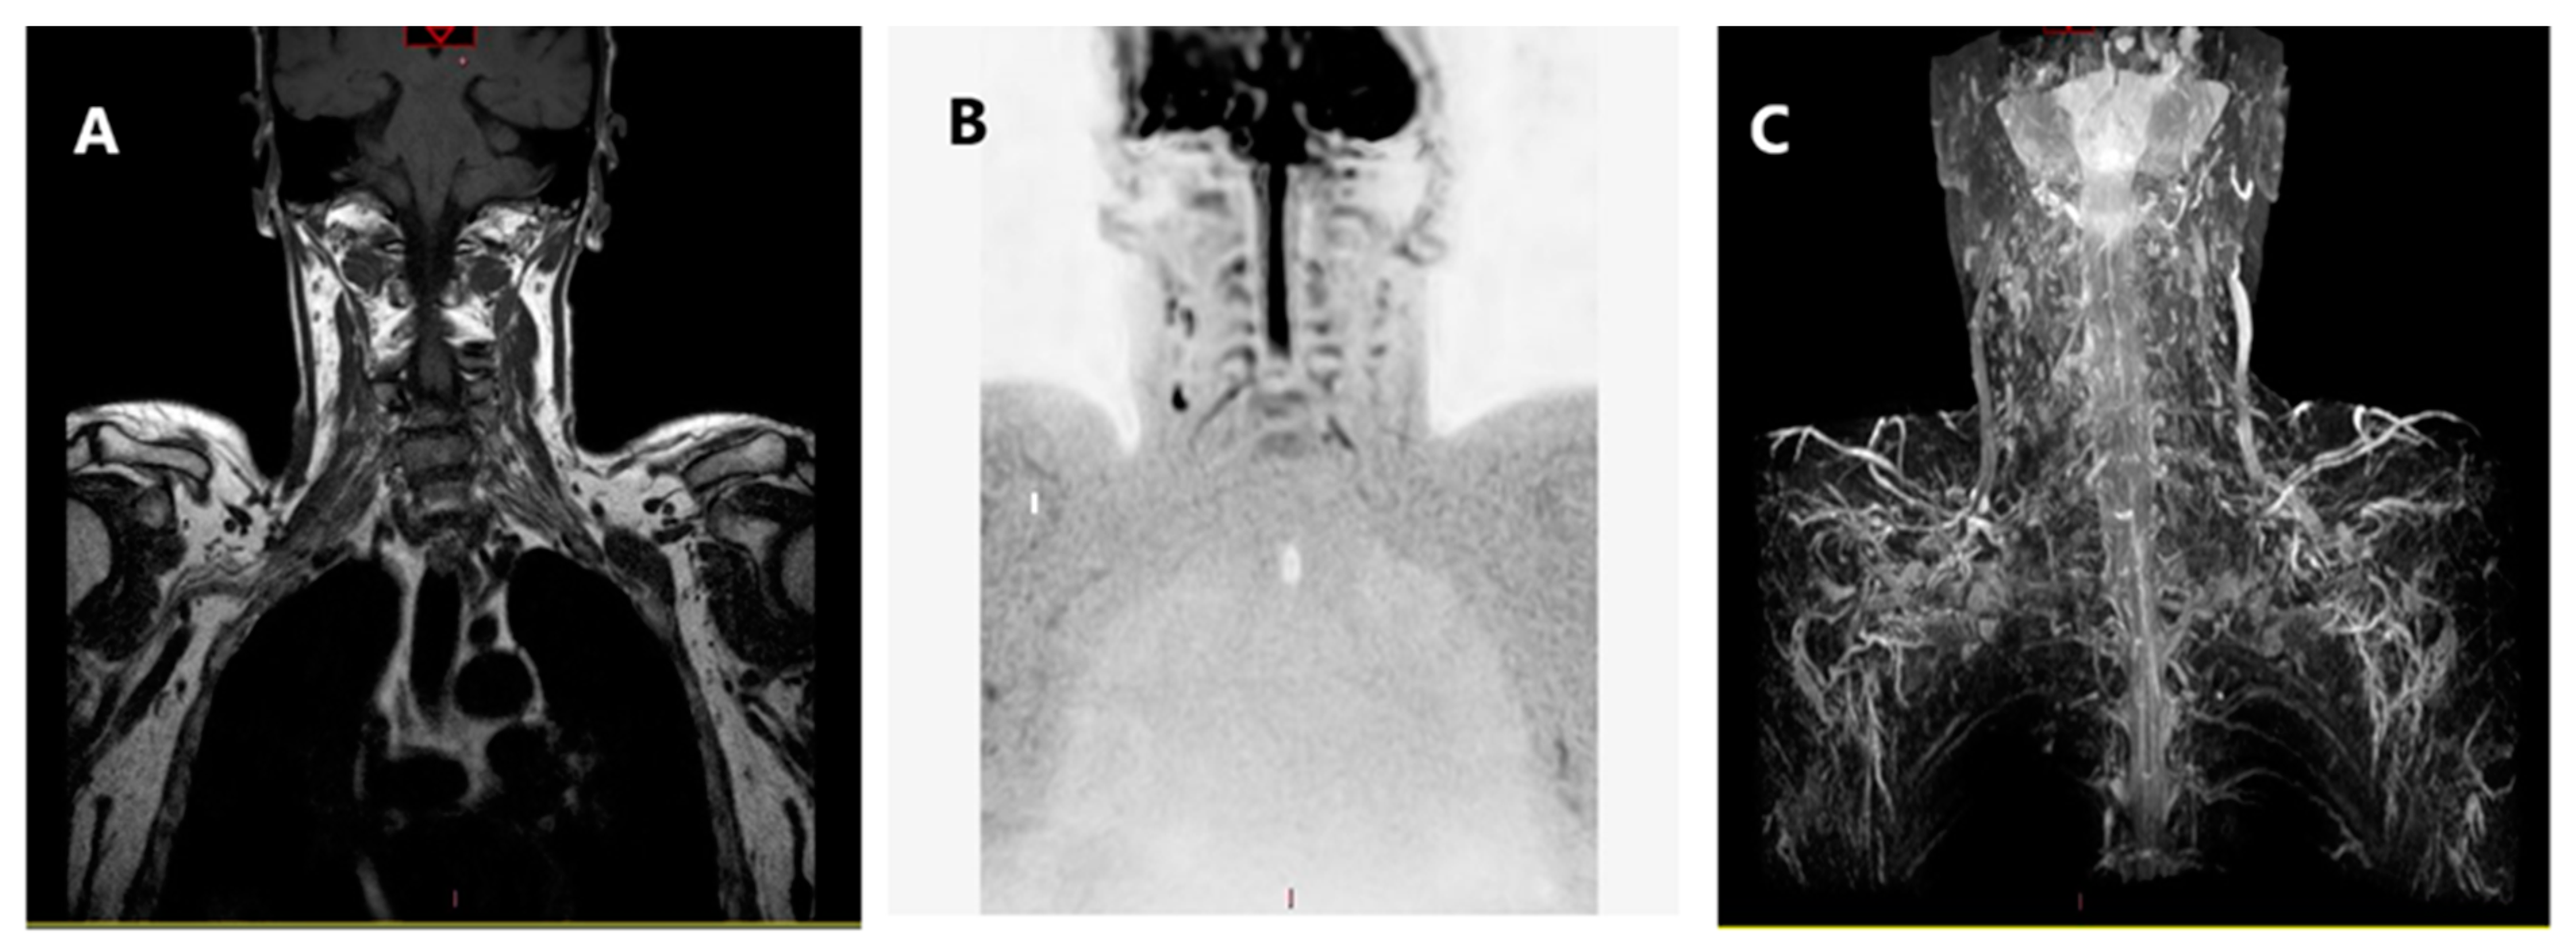

- nerve rupture: characterized by different degrees of nerve thickening caused by edema and inflammation with abnormal hyper intense signal in T2/short-tau inversion recovery (STIR) sequences;

- neuroma formation, characterized by a focal thickening of the injured segment of the nerve [17].